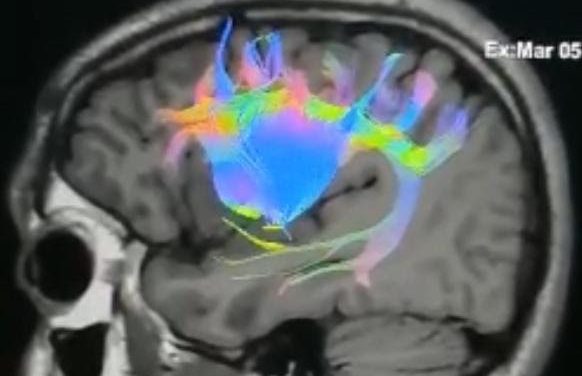

URUGUAY: LOGRAN CON ÉXITO PRIMERA NEUROCIRUGÍA DE UN TUMOR CEREBRAL CON MAPEO DE LA COGNICIÓN SOCIAL

Médicos neurocirujanos integrante de la Sociedad de Neurocirugía del Uruguay, llevaron a cabo este...